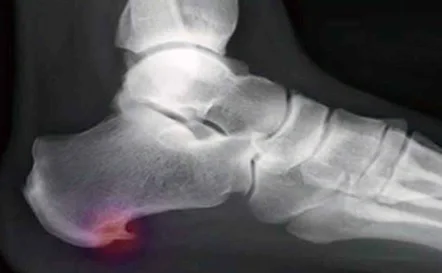

En el blog de hoy hablaremos sobre las plantillas para espolón. El espolón calcáneo se trata de una protuberancia ósea en el talón que causa dolor y malestar en el pie. Esta condición puede afectar a cualquier persona, pero suele ser más común en los deportistas y en aquellos que pasan largas horas de pie o caminando.